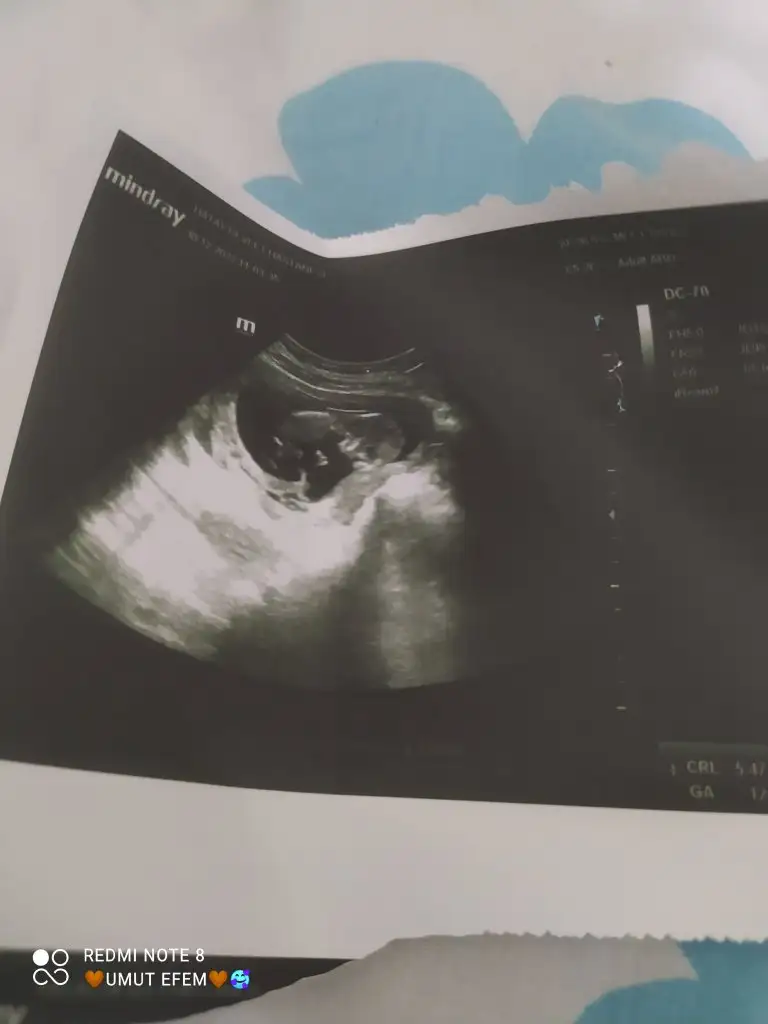

Seklinde ne var?12 haftaligim cinsiyetini söylemediler bebeğin şekli neden böyle bilen var mı keseden anliyan lütfen yardım edebilir mi cinsiyetini de merak ediyorum yardımcı olursanız sevinirim

Normalde alta olması lazım Ken yukarıda gözüküyor o yüzden cinsiyetine bakamadilarSeklinde ne var?

Benimkide 5 aylıkken öyleydi sonra döndü. Merak etme sadece öyle yeri rahat her halde4 aylik

9 haftadan beri böyle galibaBenimkide 5 aylıkken öyleydi sonra döndü. Merak etme sadece öyle yeri rahat her halde

Keyfine göre takiliyo isde9 haftadan beri böyle galibarahatı seviyor benim çocuklar ilkim ayak ayak üstüne atardı bu da değişik durmayı seviyor